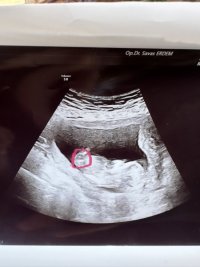

Ultrason görüntüsüne göre bebeğimin cinsiyet tahminini yapar mısınız ?

Ultrason görüntüsüne göre bebeğimin cinsiyeti ne arkadaşlarım. Ben aranıza yeni katıldım yardımcı olabilir misiniz meleklelr ?

Şu isaretledigim yere dikkatli bakabilir misiniz orası cinsiyet ama biseye benzetemedim

Selamlar bi tanem vallahi tam olarak hatta hiç bişi göremiyorum daha daha doğrusu, ilgili resimdeki veri, cinsiyet tahmini için yeterli değil. Bak hemen aşağıdaki nub teorisine göre bebek cinsiyet tahmini yapmak istiyorum ama o alan yok aşağıdaki konuyu incele bitanem.